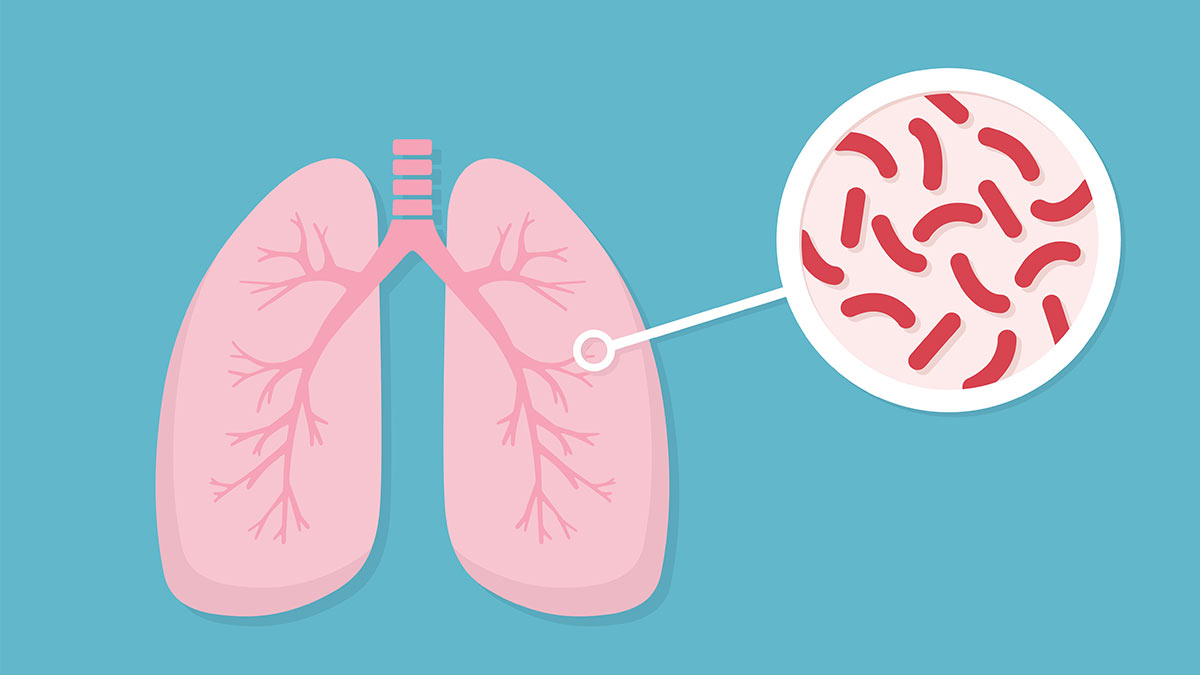

ٹی بی

ٹی بی مائیکروبیکٹیریم ٹیوبرکلوسس نامی جرثومے کی وجہ سے ہونے والا مرض ہے۔ اس کا شکار فرد جب سانس لیتا یا کھانستا ہے تواس کے جراثیم ہوا میں شامل ہوکردوسروں تک پہنچ جاتے ہیں۔ یوں پھیپھڑوں کی ٹی بی ایک فرد سے دوسرے کو لگتی ہے۔ تاہم اس کی دیگر اقسام مثلاً دماغ، ہڈیوں اورمعدے وغیرہ کی ٹی بی اس طرح دوسروں تک منتقل نہیں ہوسکتی۔ تقریباً80 فی صد کیسزمیں ٹی بی پھیپھڑوں کی ہوتی ہے، اس لئے کہ جراثیم سب سے پہلے انہی میں جاتے ہیں۔ اس کی دو اقسام زیادہ اہم ہیں۔